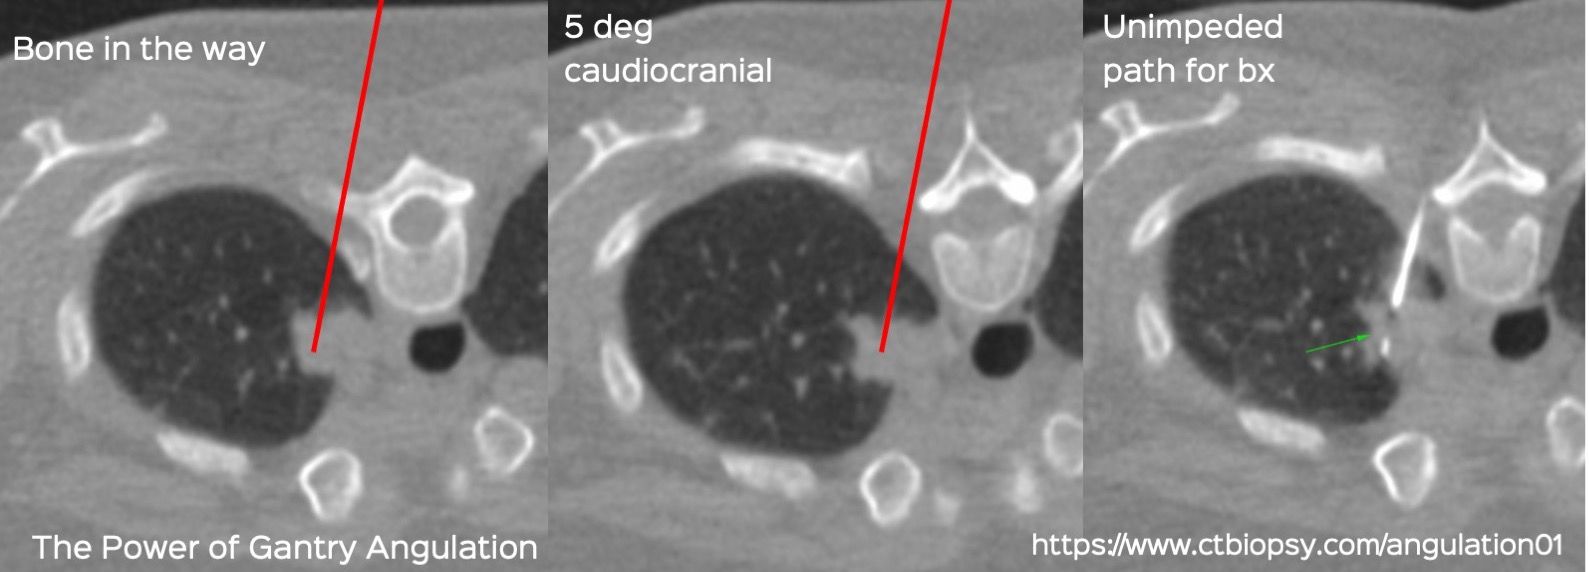

Case 81: The Power of Gantry Angulation

Bhavin Jankharia - 26 February 2022